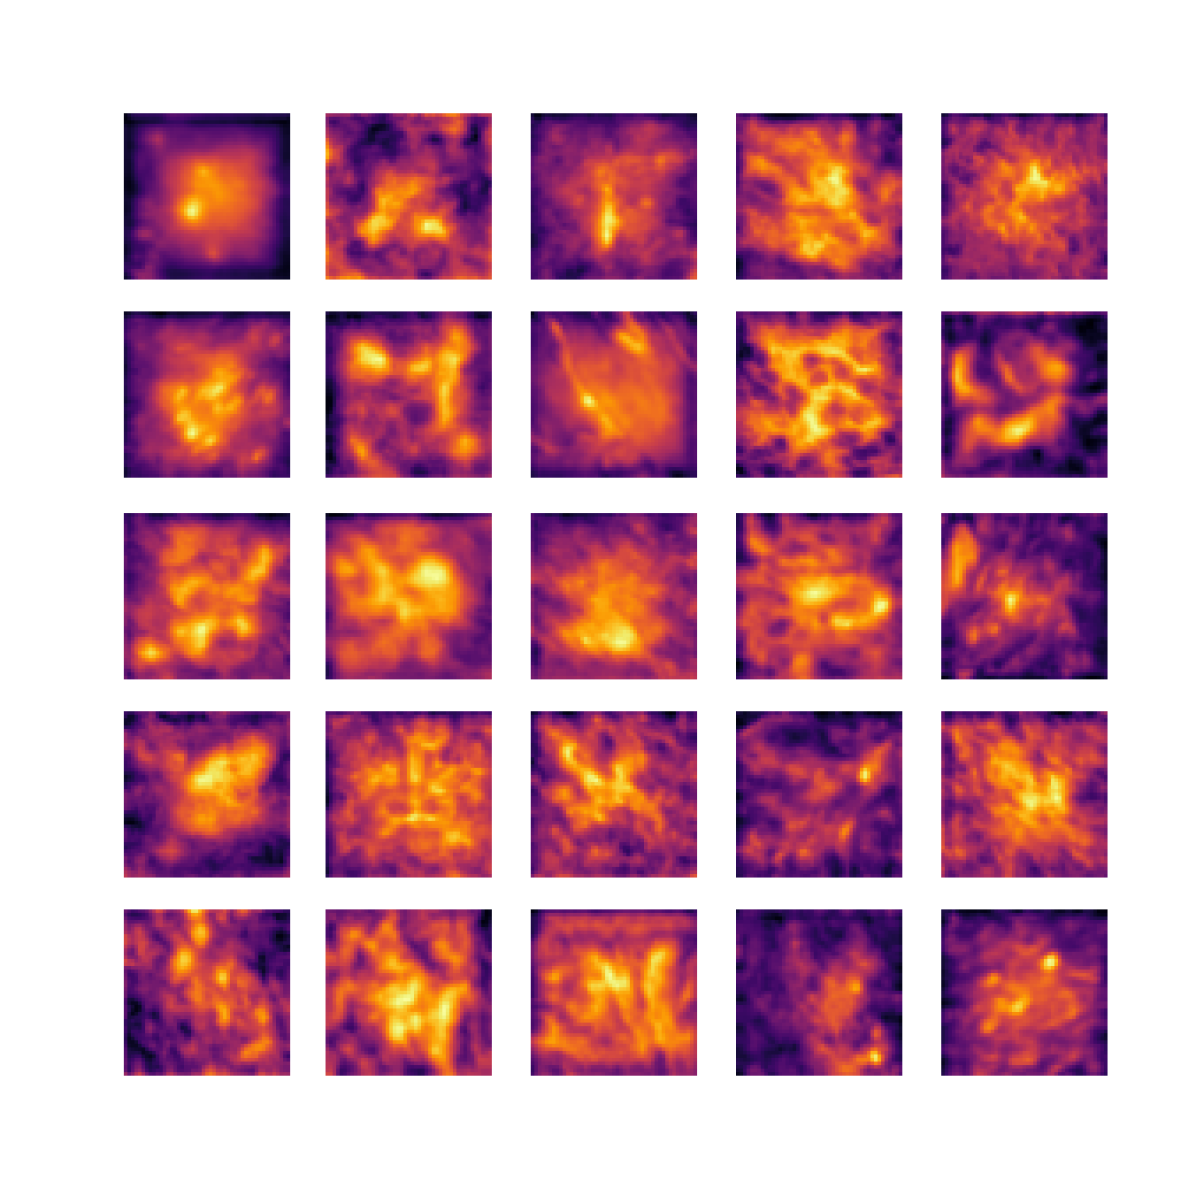

We also analyse the activation maps for each model using GradCAM as described in section S3. This offers more insight into the areas of the image which are contributing most heavily to the models’ representations. In Figure 4(b) we present some representative examples, however, a larger selection which was chosen at random is presented in Figures S10 to S25. The larger selection makes it easier to see the emergent patterns, including that privileged Siamese models tend to mainly identify features which are strongly present in both inputs, while unprivileged Siamese models tend to learn more diffuse features that are not specific to one cell phenotype or image region. TriDeNT ♆ incorporates both sets of features, learning both features specific to the privileged data and more the general features associated with unprivileged Siamese networks.

We can see in Figure 4(b) panel A that for ERG, the privileged Siamese model focuses almost exclusively on any nuclei which could be endothelial cells. As there are very few endothelial cells in the dataset, it could be an effective strategy to identify anything that could potentially be an endothelial cell to minimise the difference between the representations of the H&E model and the IF mask model. In the corresponding unprivileged Siamese image, we see that the model identifies some of these nuclei, albeit less strongly, but also focuses heavily on the other tissue and even the background, while strongly fixating on two spots of debris in the center of the image. This model has less ‘incentive’ to learn the weak features related to endothelial cells as these occur rarely and are not easy to detect, while more generic strong features such as the presence of connective tissue and the prevalence of background are more common and predictable from augmented images. We see that TriDeNT ♆ combines these two feature sets, strongly identifying nuclei while also identifying the connective tissue.

In panel C we see a similar pattern, with the privileged Siamese model fixating solely on the nuclei, while the TriDeNT ♆ model takes a more balanced approach. The unprivileged Siamese model appears to focus on a single cluster of nuclei while neglecting others, and similarly identifies an area of fibroblasts with its distinctive pattern but does not others.

In contrast to panels A and C which represent models with poor privileged Siamese results, panels B and D represent models whose privileged Siamese results were comparable to both TriDeNT ♆ and even the supervised baseline. It is therefore interesting to note that there are far more similarities between the privileged Siamese and TriDeNT ♆ models in both cases. Particularly in panel B, TriDeNT ♆ and the privileged Siamese model return virtually identical heatmaps, with both strongly identifying epithelial nuclei and neglecting the same areas of connective tissue. The unprivileged model in this case appears to focus solely on the centre of the image, giving a significantly different heatmap to the other panels.

Panel D again shows the previous pattern, with the privileged Siamese model identifying the features strongly present in the privileged data – fibroblasts – while neglecting the nuclei present. TriDeNT ♆ also strongly identifies the connective tissue, but, unlike the privileged Siamese model, does not completely neglect the nuclei. The unprivileged Siamese model primarily identifies background, and does not appear to identify the nuclei in this example.